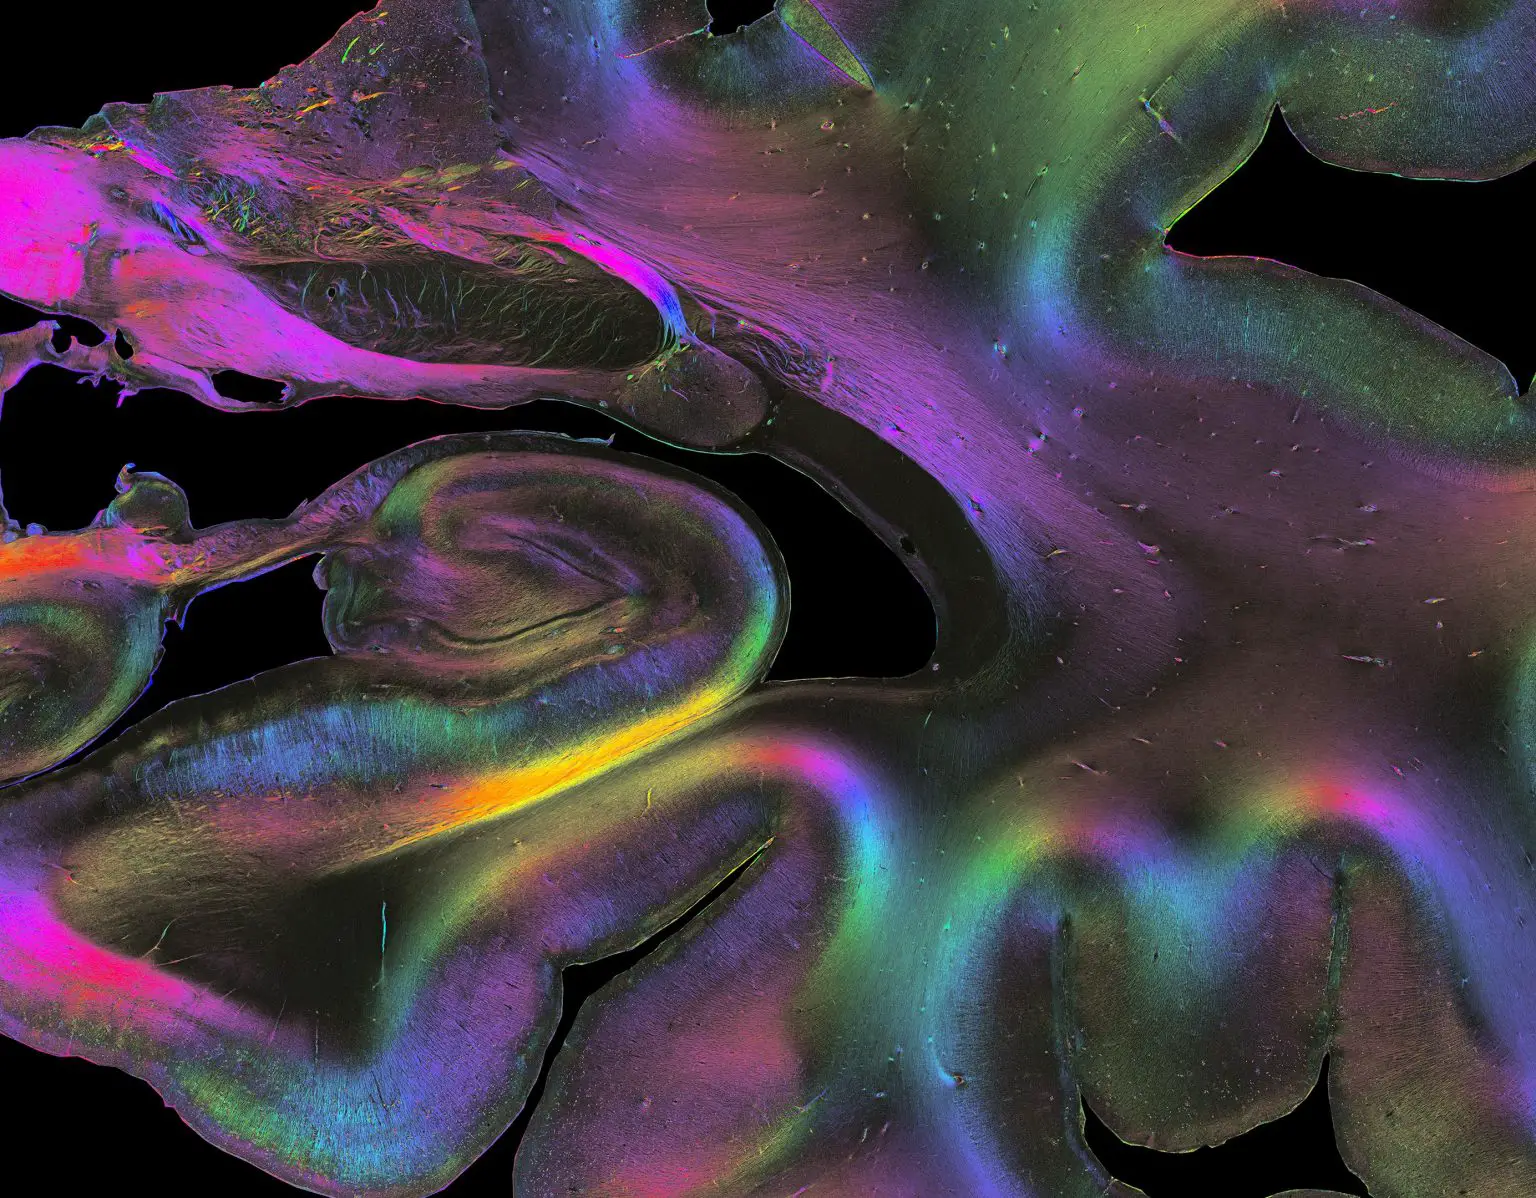

3D 偏振光成像揭示了人脑部分的细节,显示了海马体中细至单个轴突的纤维结构。 颜色代表 3D 纤维方向,突出显示单个纤维和纤维束的路径。 图片来源:Markus Axer 和 Katrin Amunts,INM-1,Forschungszentrum Jülich

来自 Forschungszentrum Jülich 和伍珀塔尔大学物理系的 Markus Axer 是科学文章的第一作者,他和他在 INM-1 的团队开发了一种称为 3D 偏振光成像 (3D-PLI) 的独特方法来可视化神经 微观分辨率下的纤维。 研究人员在连续的大脑切片中追踪纤维的三维路线,目的是开发整个人类大脑的 3D 纤维图谱。

“3D-PLI 充当微观和宏观方法之间的桥梁,”Amunts 说。 “这是因为 3D-PLI 以高分辨率解析了纤维结构,同时允许对全脑切片进行成像,然后我们可以在 3D 中重建以追踪纤维连接。”